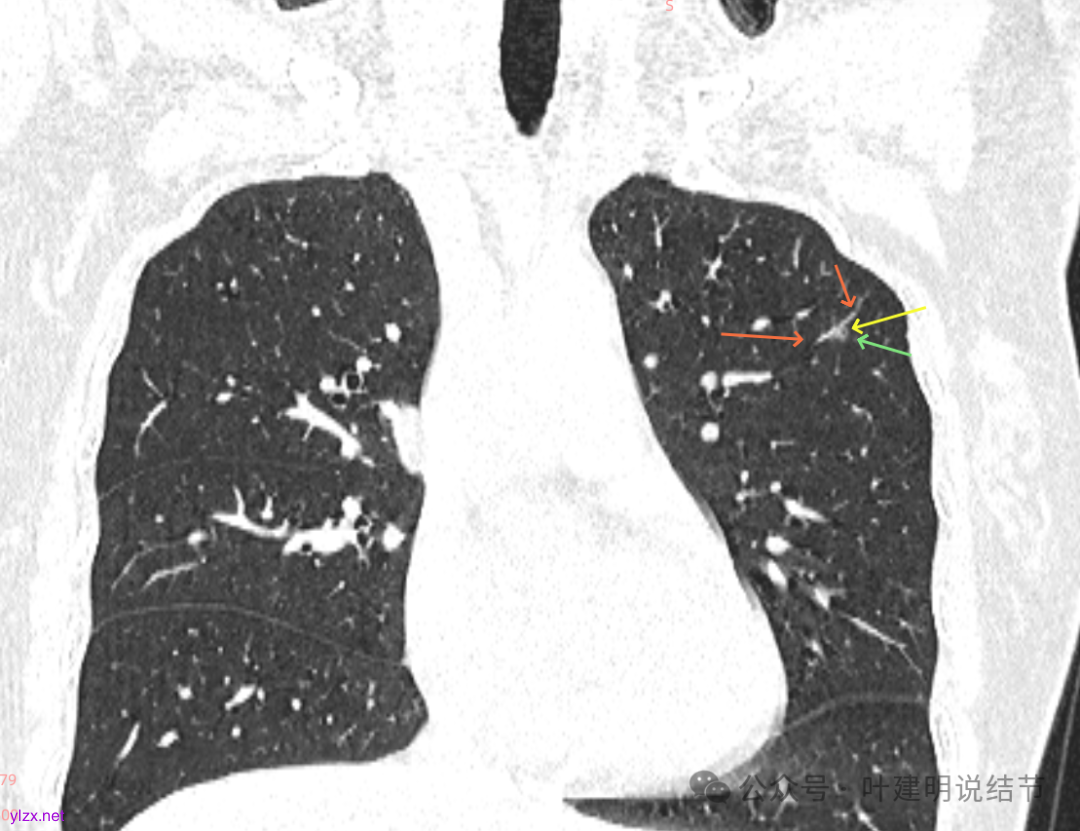

先来看2025年3月的影像:

主病灶矢状位有血管进入,边缘毛糙,密度不纯,倒是更像肿瘤些。

再看2020年5月时的主病灶以及两次对比的影像:

上图示对比,密度略有增加,但并不十分厉害。

两肺多发磨玻璃结节,我们主要看最主要的病灶有没有风险或者有没有进展就可以。我是先看2025年的,黄色的微小磨玻璃结节,密度很低,但是轮廓较为清楚,需要考虑肺泡上皮增生或者肺泡间隔增宽,严格意义上应该没有算肺癌,但是以后有可能会发展到不典型增生或者原位癌,当然也可能永远发展不到那个程度,所以目前不需要管;蓝色的到底是肺泡上皮增生还是少许慢性炎不太好确定,因为轮廓稍显模糊,但它又是磨玻璃密度,总归近期是能够随访的;橘色的密度比黄色的略高,有可能会使肺泡上皮增生或者不典型增生,目前也仍可以随访;粉色的是主病灶,位于左肺上叶,混合密度,表面毛糙,由小血管进入,单次看需要考虑微浸润性腺癌可能性较大。然后我们再来看2020年的影像,因为除了粉色的其他的都没有风险,所以不需要一一去找出来,重点关注粉色这处当时是怎样的。我们发现这个病灶5年前就有,也有小血管进入,也有表面毛糙,也是磨玻璃密度,但是当时磨玻璃当中没有实性的成分,是纯磨玻璃伴微小血管进入。对比起来看,这个病灶在5年当中略有进展,原来应该是腺体前驱病变,现在应该是原位癌或者微浸润性腺癌。那么是不是现在就到了一定得马上手术的程度呢?这个仍然可能是不同医生意见会有出入的。假如说从再随访是不是马上会转移来讲,这么小的肿瘤,发展这么慢,而且仍然含有磨玻璃成分,病理考虑与微浸润性腺癌可能性较大,应该仍然不至于说没有随访的空间。但是如果继续随反思想压力比较大,以及即便在随访后续仍然总得要开刀来说,加上病灶位置靠胸膜并不远,简单的单孔胸腔镜楔形切除就能解决问题,将有一定风险的这个病灶切了,同样是可行的。这需要你自己权衡决定。我没有办法100%给十分确切的意见。但是如果从倾向性来讲,由于是多发病灶,加上年纪还轻,风险还不是很大,稍微清一下雨6~9个月复查,有进展病风险再增加再考虑手术。意见供你参考!